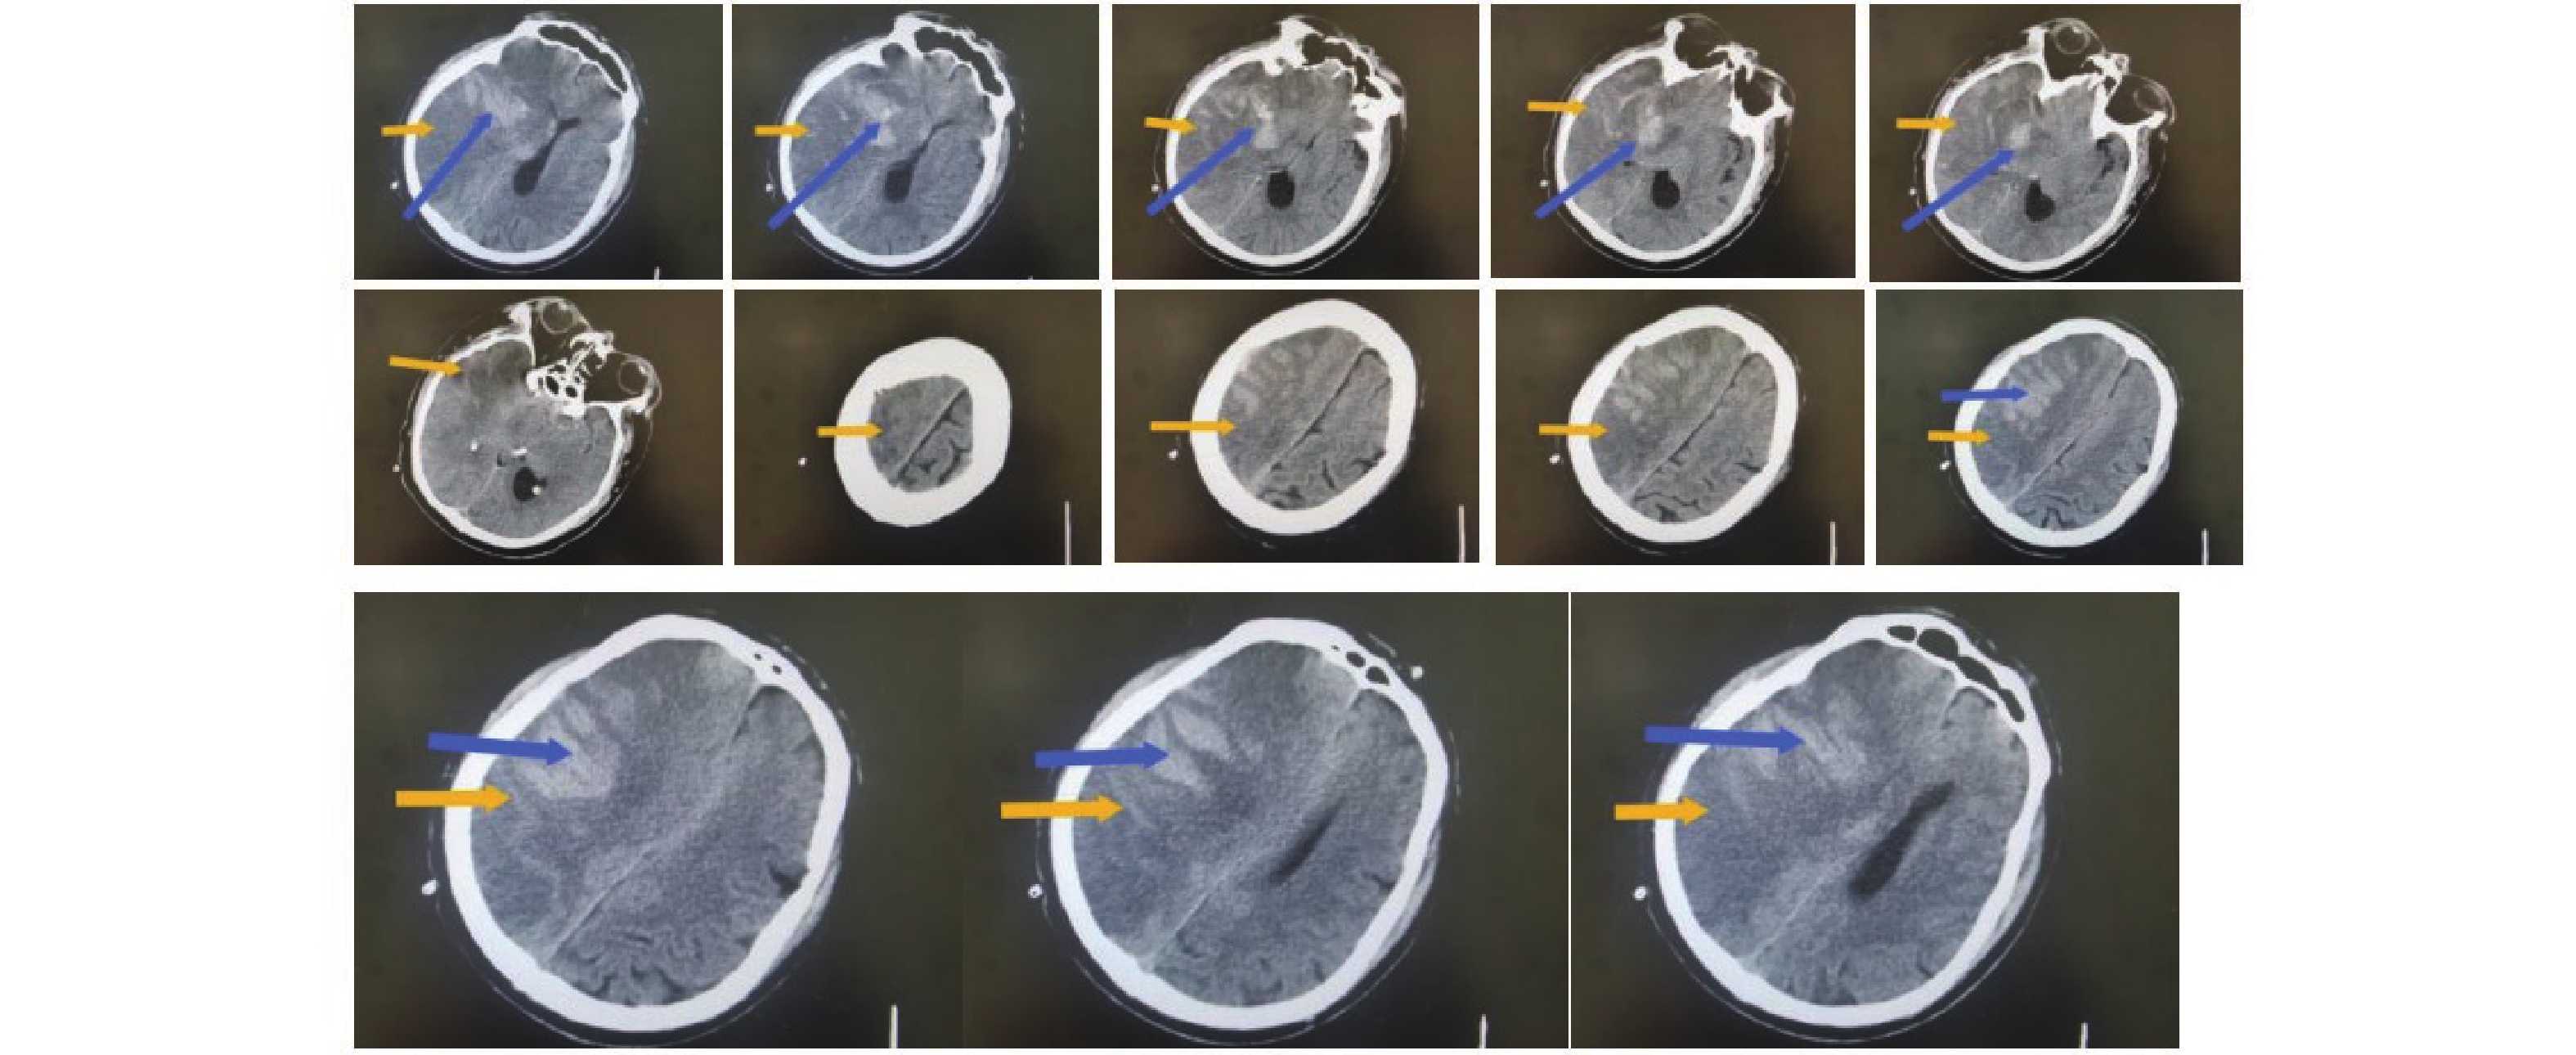

• 图  1  不良组术前头颅影像学表现

注:男性患者,67岁,从CT上看右侧额叶、颞叶、顶叶、岛叶大面积脑梗塞伴出血,中线左移,脑疝形成。其中橙色箭头指向低密度区为梗塞区,蓝色箭头指向较高密度区为出血。

Figure  1.  Preoperative cranial imaging findings in the poor outcome group

图  2  良好组术前头颅影像学表现

注:男性患者,75岁,从CT上看右侧额叶、颞叶、顶叶、岛叶大面积脑梗塞伴出血,中线左移。其中橙色箭头指向低密度区为梗塞区,蓝色箭头指向较高密度区为出血。

Figure  2.  Preoperative cranial imaging findings in the good outcome group